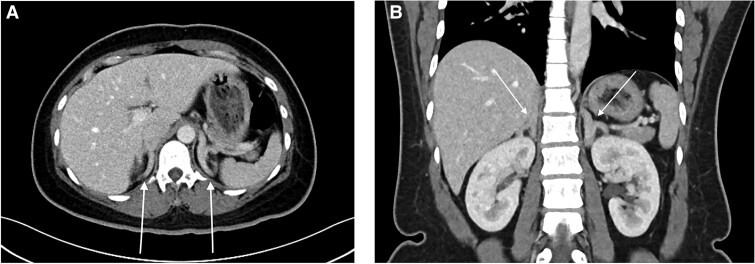

Abstract Image